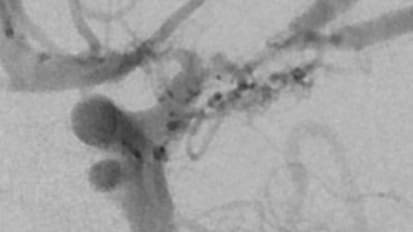

Paving a Path for Treating Pediatric Moyamoya

Johns Hopkins neurologist Lisa Sun tackles knowledge gaps in research on the rare blood vessel disorder.